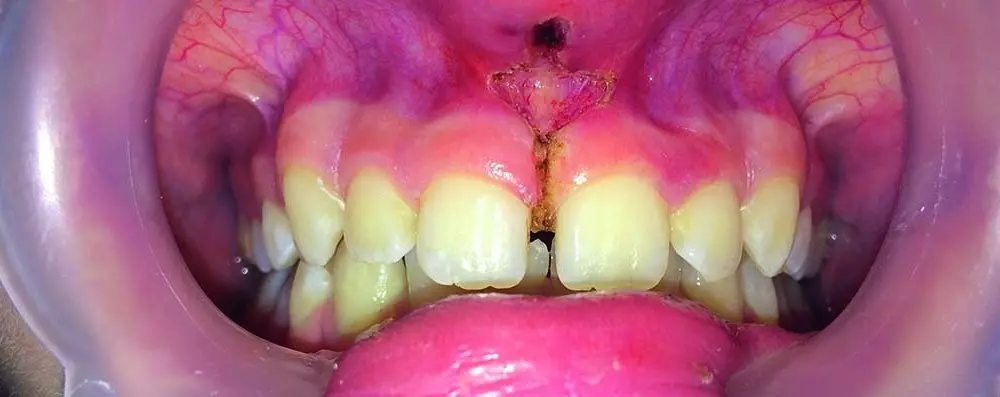

PRACTISE & CASES

- Rafał Flieger

- 31 stycznia 2020